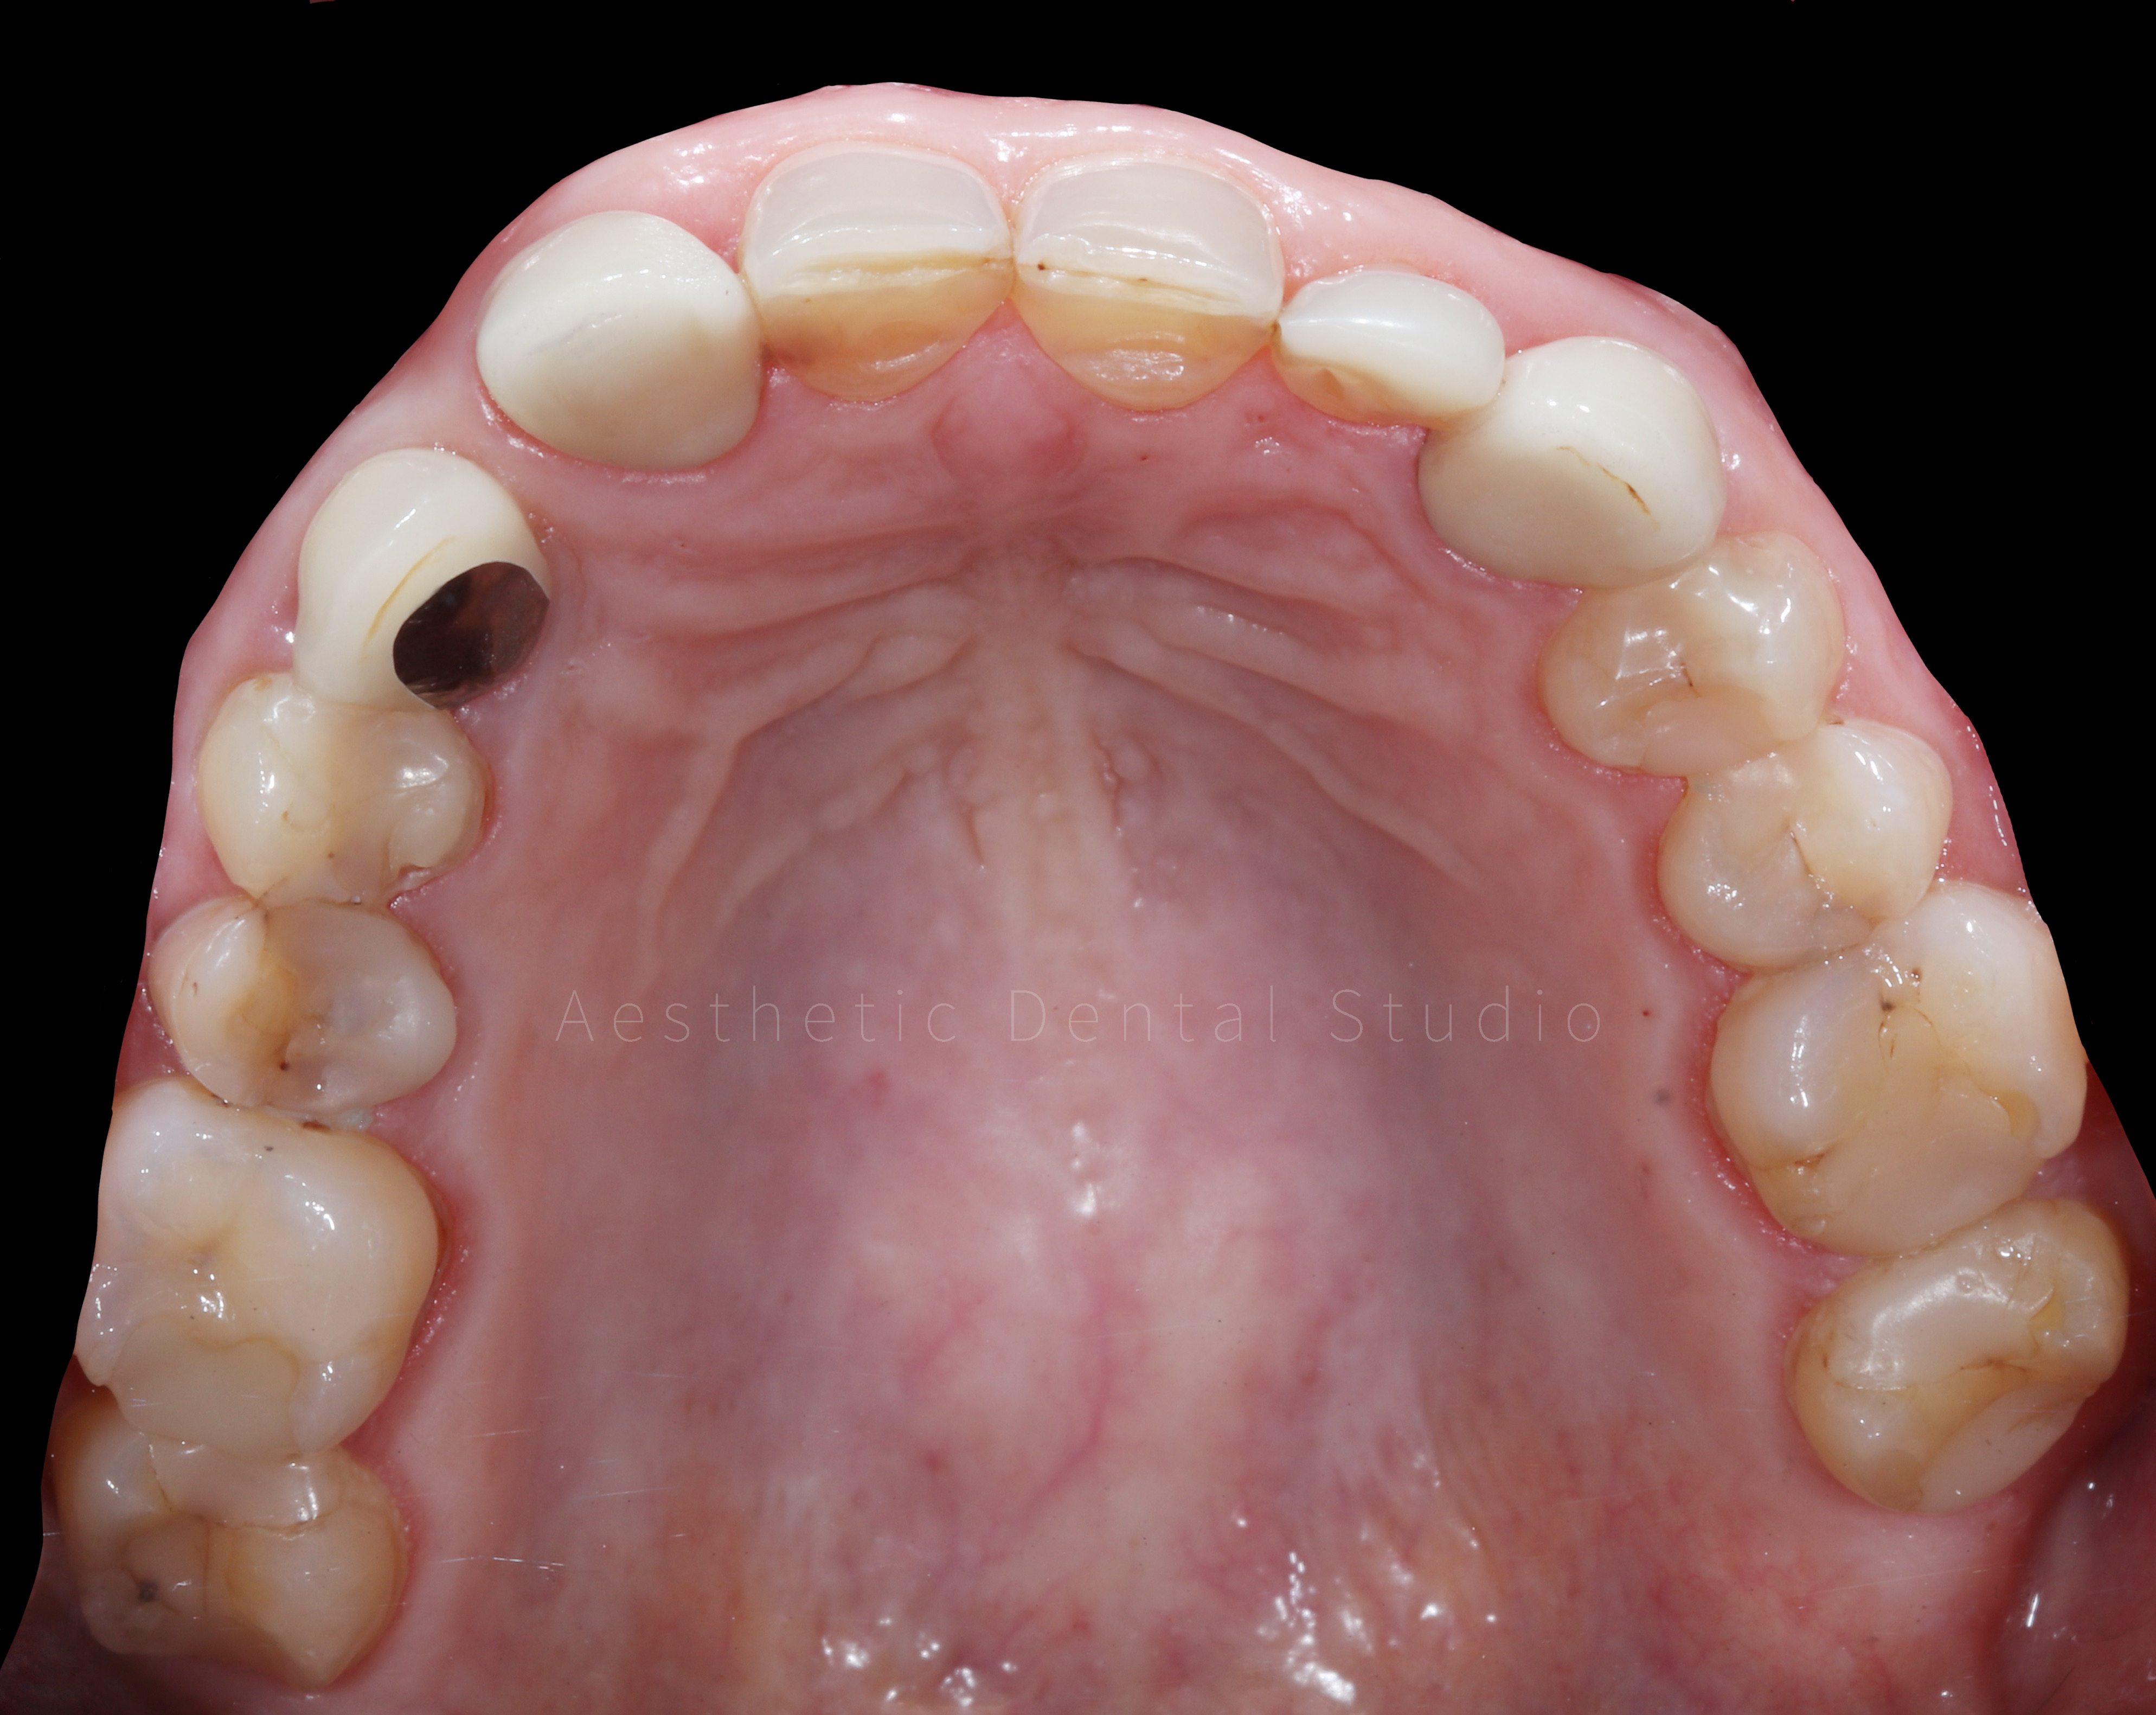

Ασθενής από τη Δυτική Ευρώπη επισκέφθηκε το Aesthetic Dental Studio κατά τη διάρκεια των διακοπών της στην Καλαμάτα, με βασικό στόχο τη βελτίωση της αισθητικής του χαμόγελού της. Η αρχική εικόνα παρουσίαζε ανομοιομορφία στο σχήμα και το χρώμα των προσθίων δοντιών, φθορά των κοπτικών άκρων και παλαιές αποκαταστάσεις που αλλοίωναν τη συνολική αρμονία του χαμόγελου. Η ασθενής ε πιθυμούσε ένα φυσικό αλλά αισθητικά άρτιο αποτέλεσμα, διατηρώντας την αυθεντικότητα των χαρακτηριστικών του προσώπου της.

Ο θεραπευτικός στόχος ήταν η αισθητική αποκατάσταση των 10 άνω προσθίων δοντιών με όψεις και ολοκεραμικές στεφάνες από ζιρκόνιο, συνδυάζοντας λειτουργικότητα και φυσικότητα. Η θεραπεία εντάχθηκε σε σφιχτό χρονικό πλαίσιο 10 ημερών, ώστε να ολοκληρωθεί εντός της παραμονής της ασθενούς στην Καλαμάτα.